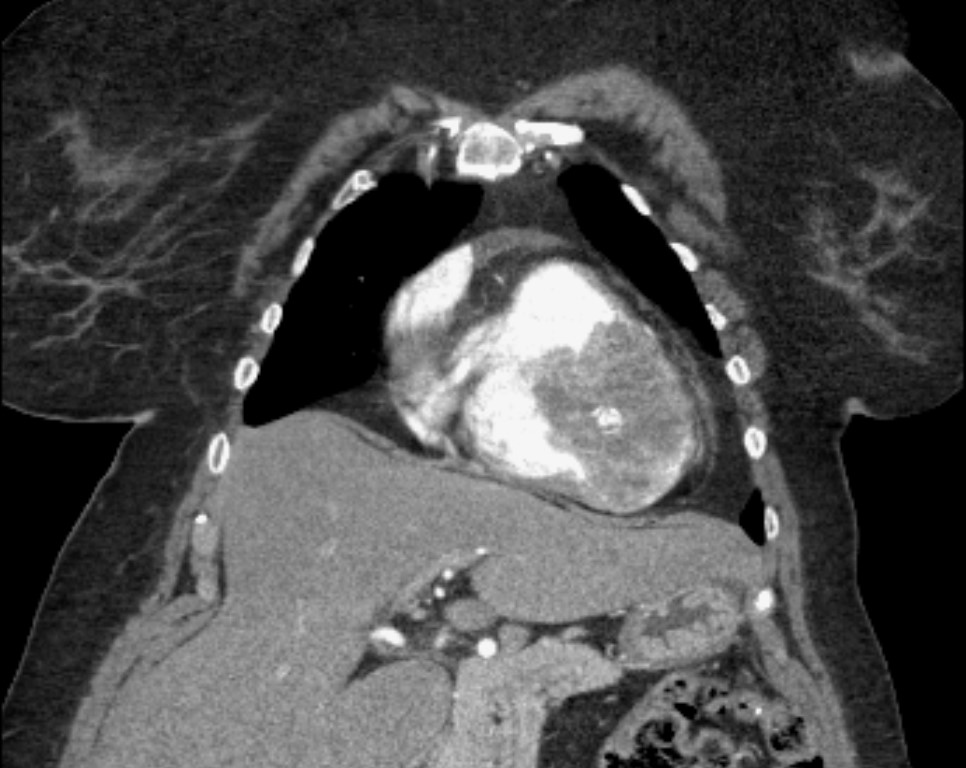

A female patient in her 60s has been followed up with annual chest-abdominopelvic computed tomography (CT) due to a clinical history of extraskeletal mesenchymal chondrosarcoma with disseminated metastatic disease. She was previously submitted to various surgical treatments, namely excision of the primary lesion located on the left thigh thirteen years before, as well as bilateral pulmonary and colic metastasectomy, left adrenalectomy and nephrectomy, splenectomy and caudal pancreatectomy in 2019. In a routine contrast-enhanced thoraco-abdominopelvic CT, a round, solid mass was found with heterogeneous attenuation, as well as internal calcifications, occupying most of the right ventricular chamber, due to heart metastasis from extraskeletal mesenchymal chondrosarcoma. It involves the right apex and almost two thirds of the ventricular septum, causing discrete bulging to the left.(Figs. 1, 2 and 3)

Figure 2: Coronal contrast-enhanced CT image shows the same round, solid mass, with heterogeneous attenuation, as well as internal calcifications, occupying most of the right ventricular chamber, in this image being more evident its apical location, as a result of heart metastasis from extraskeletal mesenchymal chondrosarcoma.